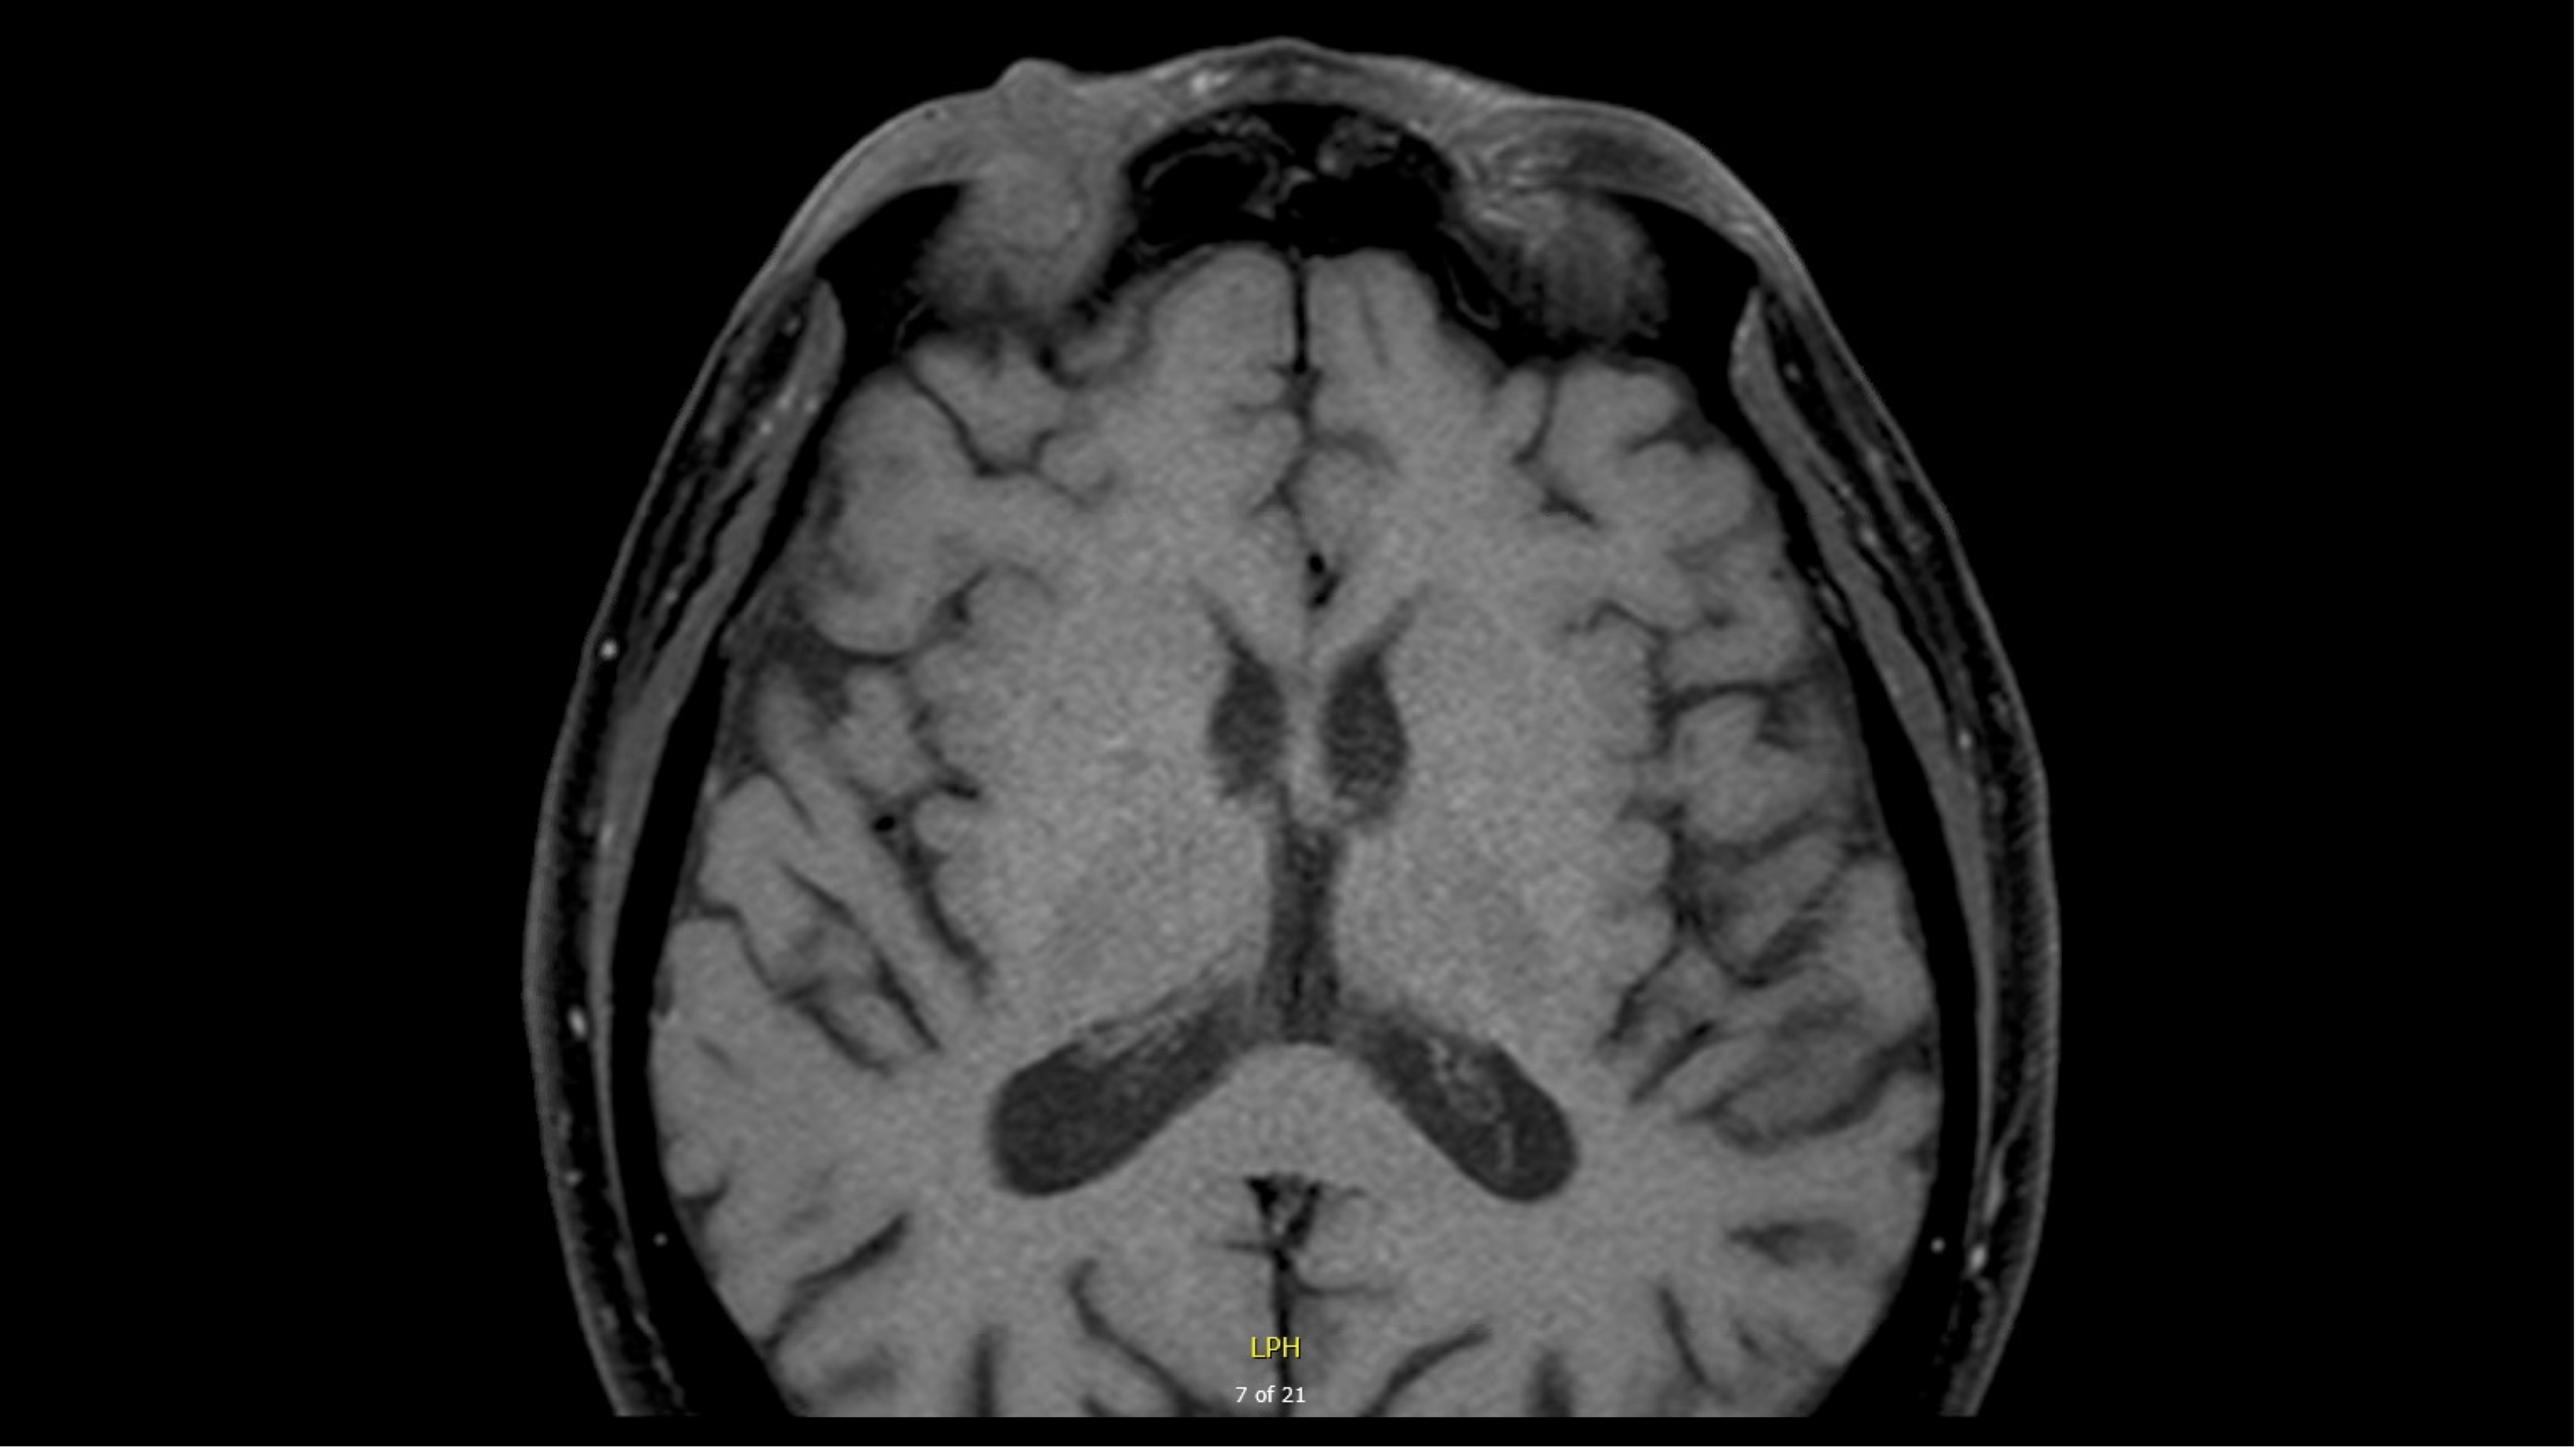

- MRI demonstrated:

T1, pre-contrast image (used with patient permission)